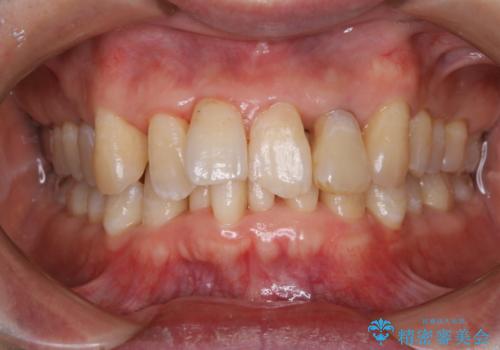

歯周病の治療前にまずはモチベーションUPにPMTCでステインの除去

- 今後、歯周病の治療を行う予定のため、まずはステインなどの除去を希望されました。PMTC60分コースを行いました。

PMTCを行うことにより、スッキリと爽快感が得られたり、見た目も清潔感のある状態になるため、今後の治療などに対するモチベーションUPにも繋がります。